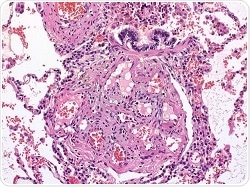

Lung tissue with lesions caused by pulmonary hypertension. Credit: Wikimedia courtesy of Bulent Celasun, MD